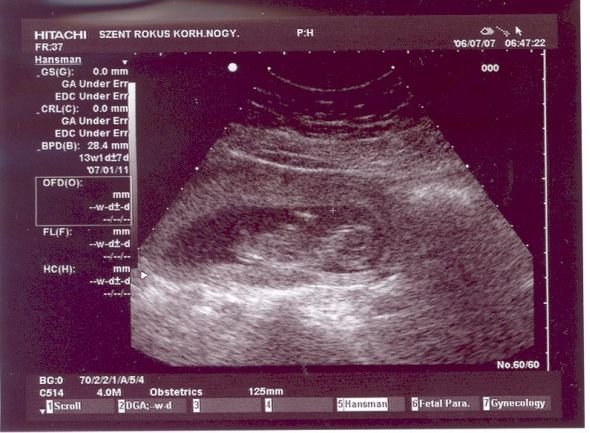

ne aggódj, minden rendbe lesz... Néha nem jó, hogy ennyire előrehaladott a technika. Nekem is ugyanezt a szöveget írták, mint neked "Az érvényben lévő szakmai protokoll szerint elvégzett vizsgálat során jelenleg durva eltérés nem ábrázolódott. Az aktuális CRL alapján, az érvényes protokoll szerint ..." Ez valószínű amiatt van, hogy ha netán baj van, a kórház védi magát... de lehet, hogy volt már valamilyen perük...

Nekem is anno észrevettek egy amnionszalagot... Aztán voltam a Praxisban, de úgy, hogy egy nappal előtte a rendes dokim látta a szalagot, a Praxisban meg azt mondták, hogy nincs sehol... Na akkor most mi is van....